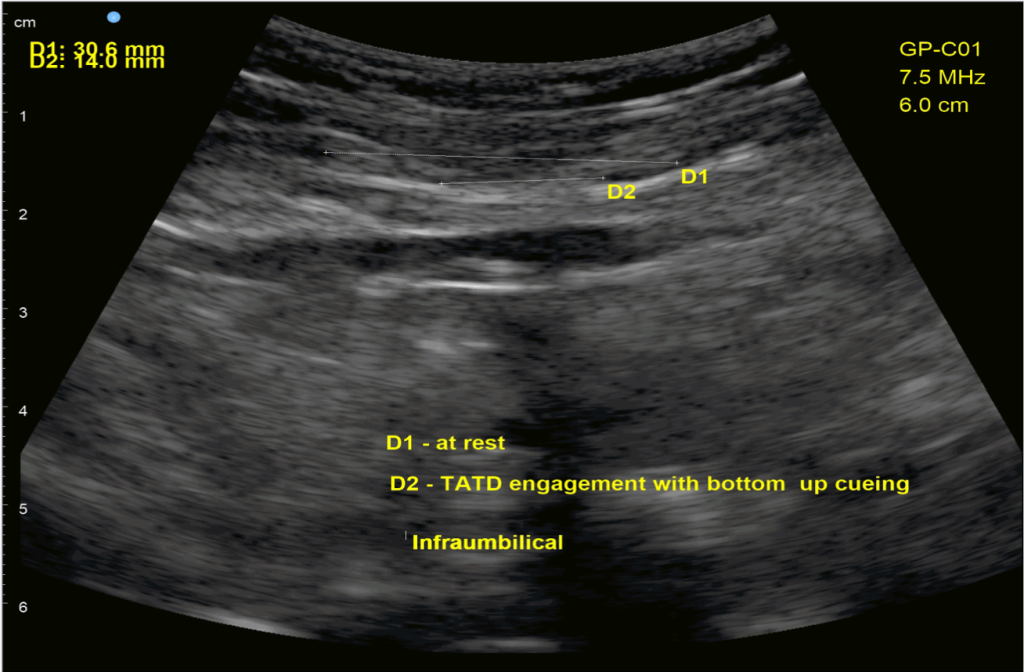

In the first image, I am cuing Umbrella Breath using the pelvic floor to initiate the breath. The patient was able to positively impact her diastasis rectus abdominis (abdominal split), which did carryover to improved daily function and strength (because closure of the split isn’t what is most important). However, when she too rigidly held the abdominals, which can be common when first learning how to do Umbrella Breath, pelvic floor function suffered.